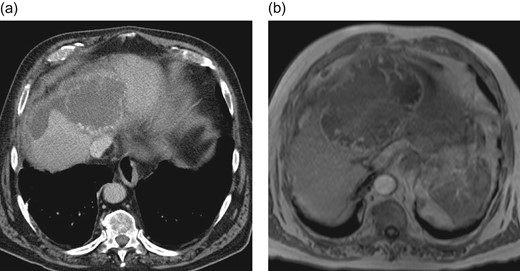

An elective control computed tomography scan (Fig. 1a) in April 2016 revealed constant hypervascularized lesions still not showing signs of hepatocellular carcinoma. Because of a suspected atypical hepatocellular carcinoma, an additional magnetic resonance imaging (MRI) study was performed (Fig. 1b) and a surgical resection was indicated. The intraoperative exploration showed a large central tumor of the liver infiltrating the left lobe and surprisingly the diaphragm. Extended left hemihepatectomy with partial resection of the diaphragm, cholecystectomy and biliary reconstruction by an end-to-side hepaticojejunostomy was performed on 3 May 2016 (see Fig. 4, resection line and tumor-location).

Preoperative CT-scan (a) and MRI (b) of the liver showing hypervascularized hepatic lesions with central necrosis and associated hematoma.

In CT scan and MRI choriocarcinomas present as hypervascularized liver lesions. In differential diagnosis liver adenomas, liver hematomas, hepatocellular carcinomas or secondary liver malignancies have to be taken into account. In adults its differential diagnoses can be metastatic liver tumor or intrahepatic cholangiocarcinoma [7]. In children it often mimics other benign and malignant childhood liver tumors [2].